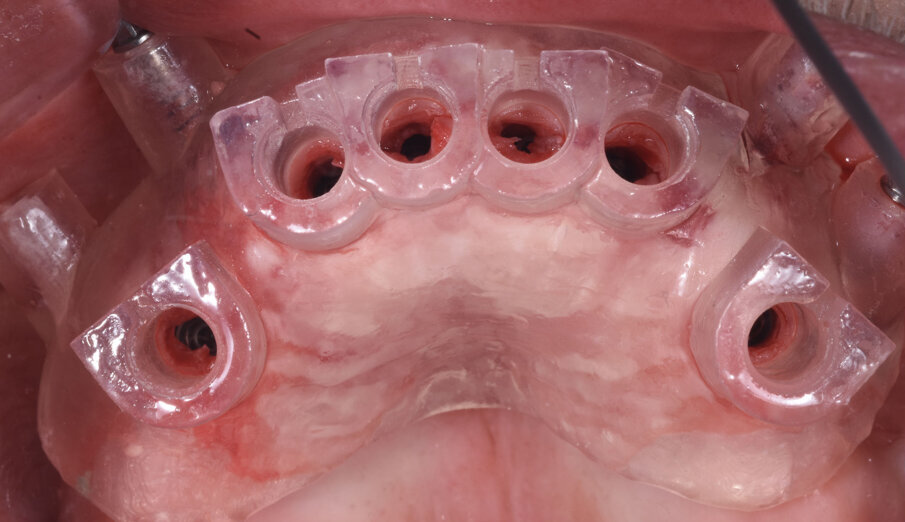

Conseguentemente allo studio effettuato con R2Gate l’azienda produce una guida chirurgica, in questo caso ancorata all’osso residuo, che consente l’atraumatica inserzione degli impianti (Fig. 5). Le fixtures, in questo caso impianti AnyRidge Megagen venivano inserite nelle posizioni designate dallo studio R2G in maniera completamente atraumatica (Fig. 6). La misurazione dell’ISQ (Implant Stability Quotient) confermava con letture superiori a 70 la possibilità di procedere con il carico immediato degli impianti stessi (Fig. 7). Il laboratorio aveva già preparato la struttura con le caratteristiche desiderate dal paziente e dopo l’inserzione dei MUA (Multi Unit Abutments) procedeva alla costruzione della protesi definitiva (Fig. 8).